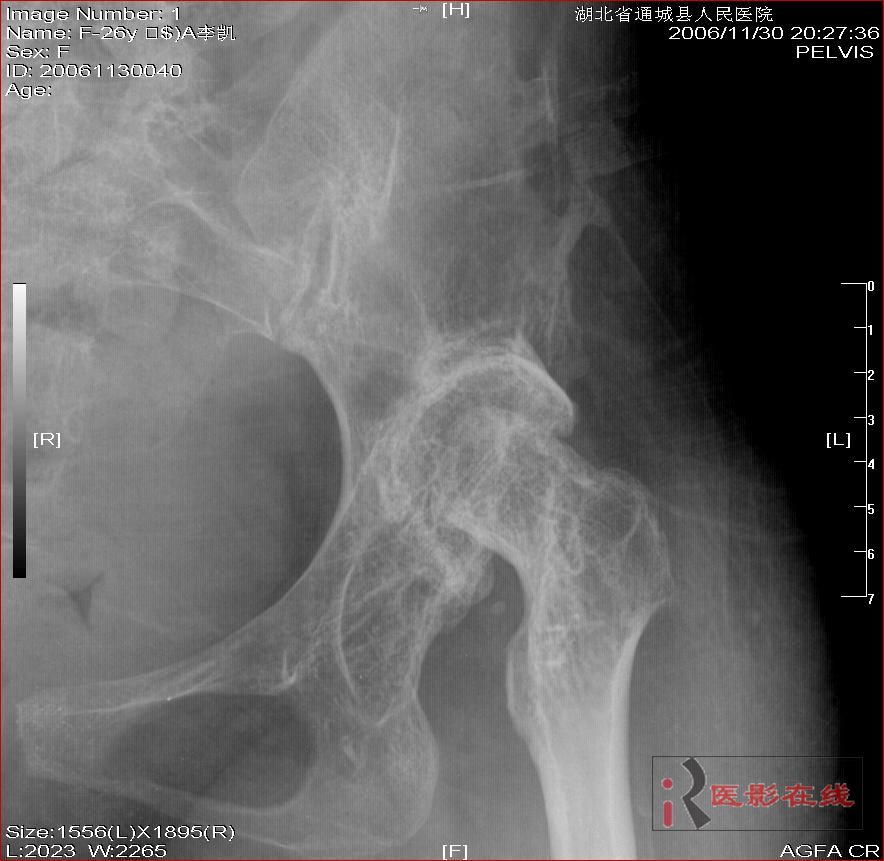

先天性双髋关节脱位自体骨关节再造

女 28岁 先天性髋关节脱位术后复查片(手术日期是2000年,数字化以前平片资料患者外带),现无其它不适,走路仍需双拐

2006年11月30日

髋关节脱位自体骨关节再造术后,股骨头发育不良,骨质疏松

1.双髋关节先天性脱位术后改变;2.双髋关节退行性变;3.骨质疏松(骨盆明显)。

双侧髋关节仍为脱位表现,假关节形成,部分已经强直,右股骨头碎裂,股骨干近端增粗。

结合手术史考虑:原地臼盖成形术后,髋关节退变,股骨头无菌性坏死,右股骨近端生长紊乱,骨质疏松。